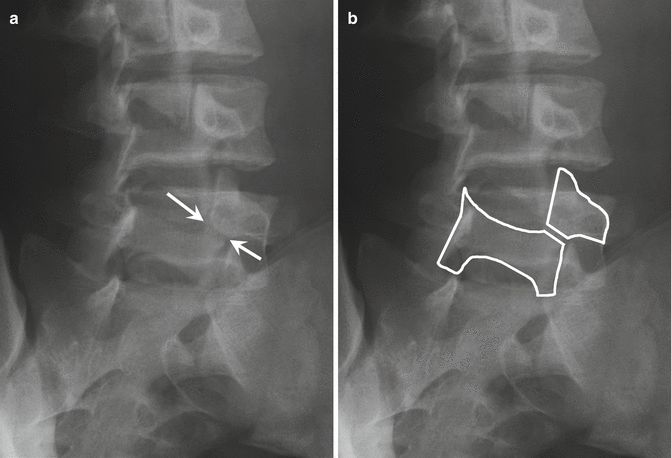

腰椎峡部在腰椎斜位片上常比喻为苏格兰狗(Scotty dog)的脖子

椎弓崩裂征象:X线腰椎45°斜位摄片示上关节突轮廓似"狗耳",横突似“狗头/嘴”,椎弓根似“狗眼”,下关节突似“狗前肢”,关节突肩部或称峡部似“狗颈部”。椎弓峡部崩裂时,“狗颈部”可见裂隙。

腰椎斜位片上的苏格兰狗和断裂的脖子(峡部裂)

再回顾下腰椎斜位视角的模式图,圆圈处为峡部